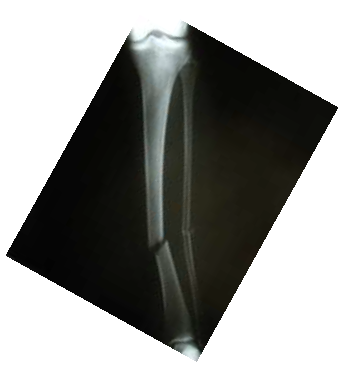

Assinale a alternativa que apresenta o diagnóstico da radiografia acima.